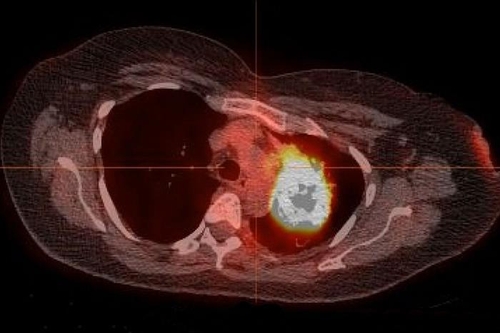

미국 연구팀 "비흡연자 폐종양서 치료가능 변이 다수 발견"

(서울=연합뉴스) 이주영 기자 = 전체 폐암 환자의 10~25%는 담배를 피운 적이 없는 사람으로 알려져 있다. 이런 흡연 미경험자 폐암의 약 80%는 미국 식품의약국(FDA) 승인을 받아 사용되고 있는 기존 변이 표적 항암제로 치료가 가능하다는 연구 결과가 나왔다.

미국 워싱턴대 의대 라마스와미 고빈단 박사팀은 1일 의학저널 '임상 종양학 저널'(Journal of Clinical Oncology)에서 담배를 피운 적이 없는 폐암 환자의 폐종양에서 종양 성장을 촉진하는 것으로 알려진 유발 변이(driver mutations)를 다수 발견했으며 이런 폐암의 78~92%는 FDA 승인을 받은 변이 표적 항암제로 치료할 수 있다고 밝혔다.